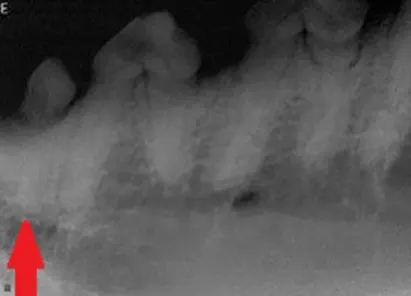

Dental radiograph of the left mandibular premolar teeth in a dog showing a classic example of canine tooth resorption.

Diagnosis: When tooth resorption (TR) is seen on routine dental radiographs, the next step is to carefully evaluate the tooth with a dental explorer along the gingival margin and look for clinical evidence of resorption (a sticky or rough area at or just below the gum line).

Treatment: If clinical evidence of resorption is found, the tooth should be extracted. If there is no clinical evidence of a lesion, radiographic monitoring is acceptable, as root resorption is reported to be non-painful in humans.

Extractions of these teeth can be challenging due to the high degree of ankyloses and resorption, and referral to a veterinary dentist is strongly recommended. Crown amputation is not a recognized treatment for these lesions; however, the first premolar tooth (red arrow) may be a candidate, as the end of the root appears isolated from the rest of the tooth and completely surrounded by new bone.